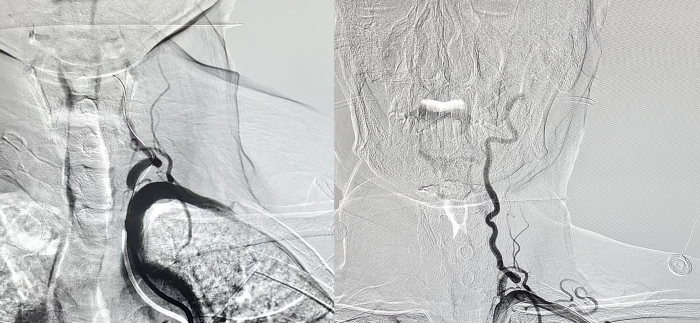

爲明确病變血管,制定下一步診療計(jì)劃,王建強團隊與張某及家屬充分(fēn)溝通并取得(de)同意後,決定行腦血管造影(yǐng)術(shù)+左側椎動脈支架植入術(shù)。

手術(shù)過程順利,患者全程清醒,無疼痛與不适感,術(shù)後安返病房(fáng)。

腦血管支架植入術(shù)是一種微創介入治療,主要用于治療腦血管狹窄或閉塞引起的缺血性腦卒中。該手術(shù)是在DSA(數字減影(yǐng)血管造影(yǐng))的引導下,通過在股動脈處穿刺置管,将導絲和導管導引至狹窄的腦血管處,然後将一個網狀中腔折疊的鎳钛合金支架通過導管送至病變部位,并在體(tǐ)外操作(zuò)下使支架自(zì)行膨脹、打開,從(cóng)而将狹窄的血管擴開,增加血流量,保證腦部血供需求。